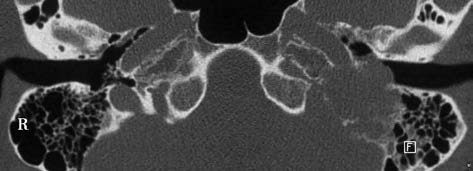

Figure 1 Axial CT features of a glomus jugular tumor of the temporal bone

Bone destruction and lytic changes are visible in the left jugular foramen region. The tumor invades the mastoid, external auditory canal, and tympanic cavity.